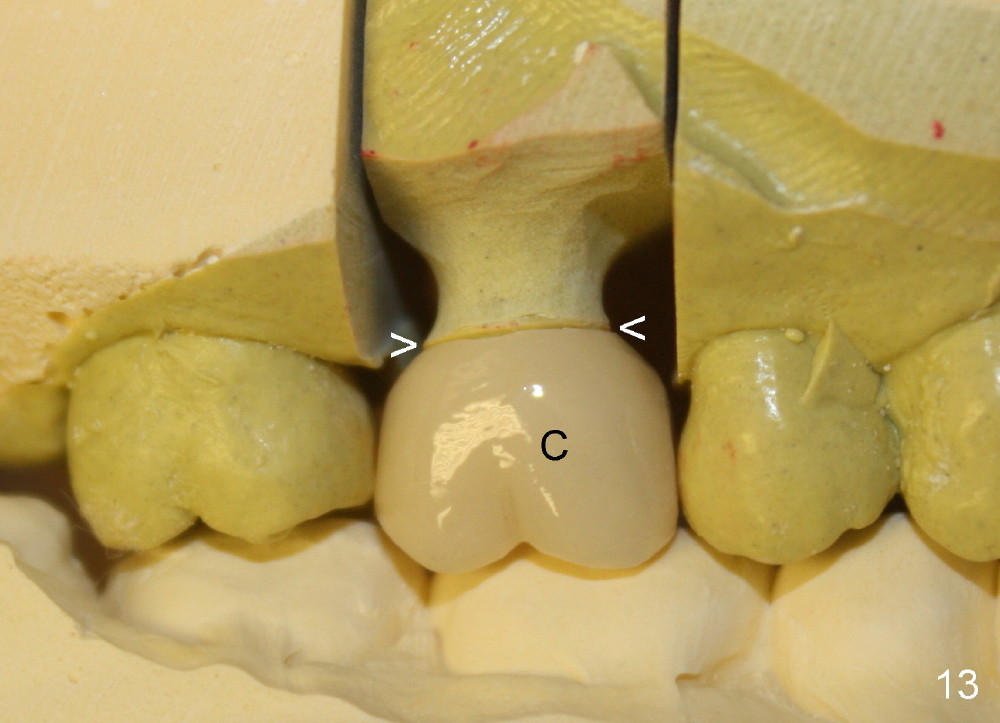

The tooth #3 has a crack line (Fig.1 ^). The septum (Fig.2 S) looks like an inverted pyramid (Fig.3), coronal part being pointed, whereas the apical broad. The shape of the septum is not so favorable to placement of tapered implant. Osteotomy starts with 1.5 mm pilot drill in the middle of the septum, followed by round tapered osteotomes 2 and 3 mm. The osteotomy begins to deviate into the mesiobuccal socket. The same osteotomes are used to re-direct the osteotomy palatally, followed by tapered drills, trying to move osteotomy palatally. A 4.5x17 mm tap is inserted with stability (Fig.4). Following using 5x17 mm tap at the depth of 12 mm, a 5.3x12 mm bone-level implant is placed ~ 1.5 mm below the crest, 1.5 mm above the septum (Fig.5). Demineralized cortical human allograft is placed in the remaining sockets and around the most coronal aspect of the implant (with a small piece of gauze placed in the implant well). After removal of the gauze, a piece of collagen membrane is pierced and carried by a 8.2x4/3 mm healing abutment and fixed in place (Fig.6 M). The periphery of the membrane is tucked underneath the gingiva. The wound is covered by perio dressing. The patient returns to clinic for follow up 8 days postop. There is no discomfort. In order to protect the collagen membrane (Fig.6), the perio dressing is intentionally not removed (Fig.7). Two weeks postop, the patient remains asymptomatic. After perio dressing removal, the membrane appears to have been resorbed (Fig.8 as compared to Fig.6). The bone graft (B), although exposed, remains in place and condensed, surrounded by healing healthy gingiva (*). The patient returns 2.5 months postop. The implant appears to osteointegrate (Fig.9, as compared to Fig.5). The buccal (Fig.10) and palatal (Fig.11) gingiva adapts to the healing abutment. When the healing abutment is removed for restoration 3 months postop, the gingiva looks healthy (Fig.12). A cemented abutment (5.8x4(2) mm) is placed; a crown is fabricated (Fig.13). The patient returns for recall 5 months post cementation. He reports food impaction distal to the crown. The gap mesial to the implant has closed (Fig.14).

Placement of a relatively small implant (~5 mm) may not damage the coronal aspect of the septum as much as a large one (6-8 mm). The socket can be closed for the most part by using a large healing abutment (8, 9 mm). Since the socket is oval in shape (Fig.3), collagen membrane (Fig.6 M) or released flap is supplemented to close the socket completely. A potentially more secure method to close the socket opening is to place a wide temporary abutment (ø 5.8 mm) and fabricate an immediate provisional, which is infraocclusal.